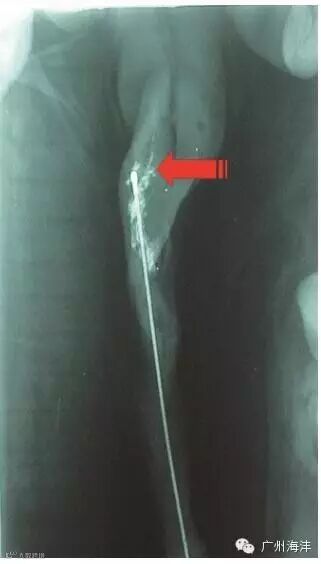

子宫内输精(Post Cervix Artificial Insemination ,PCAI),业内也称之为深部输精,是在将泡沫头型输精管插入到位并锁紧后,将一硬度适中的细管插入输精管,再将细管头部捻入到子宫颈与子宫的结合部位。细管尾部插接精液瓶或精液袋后,即可将精液用力挤入,精液沿细管并通过细管头部两侧的射精孔射入双侧子宫角,快速完成输精操作。法国IMV (卡苏)公司率先将子宫内输精技术商业化,并与1999年将子宫内输精管推向市场。